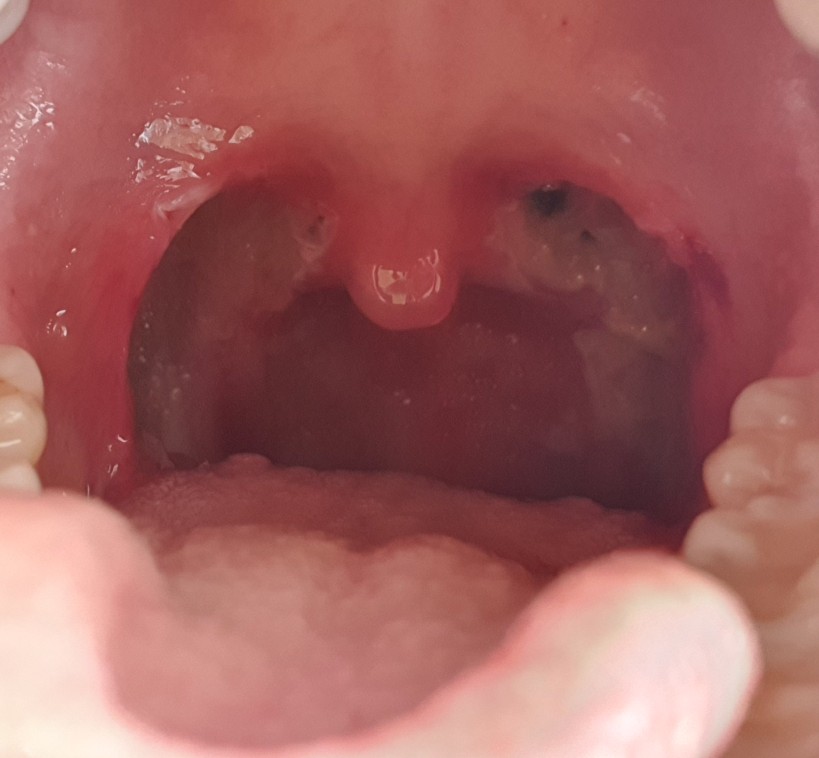

이것은 수술 전 내 편도선 자식의 사진으로 크기는 그리 크지 않았지만, 여느 편도보다는 비대해진 것이었다.

아주 깨끗이 제거했어ㅜㅜ 감사합니다!!! 하지만 보이는 검은 점? 빨간 상처?가 조금 불안해출혈은 안돼! 절대 지켜줘!!!!